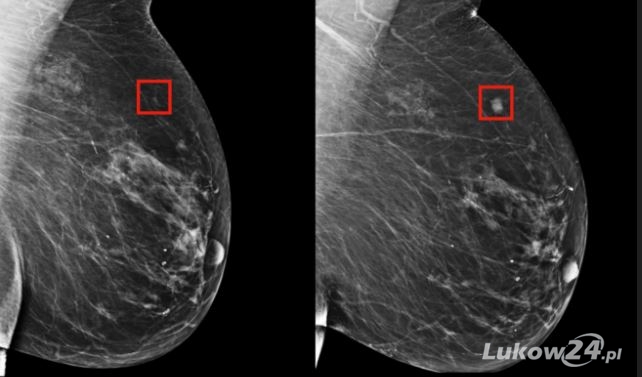

Mammografia jest prześwietleniem rentgenowskim z użyciem niskiej dawki promieniowania, dzięki któremu można zbadać piersi i wykryć w nich ewentualne zmiany. Do jej wykonania nie potrzebujemy znieczulenia, a obecne na rynku aparaty wykrywają nawet milimetrowe zmiany. Badanie wykrywa wczesne zmiany nowotworowe u kobiet, które nie zgłaszają żadnych niepokojących objawów ze strony piersi.